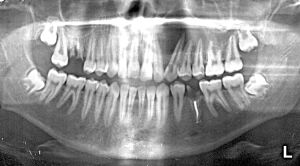

ОРТОПАНТОМОГРАФИЯ (панорамная томография) (рис.2) – метод, позволяющий получить изображение изогнутого слоя на плоской рентгеновской пленке. Во время съемки трубка и кассета с пленкой описывают неполную окружность вокруг головы больного (270є). Кассета при этом вращается еще вокруг собственной вертикальной оси, как бы «обкатывая» челюсти больного спереди. Рентгеновский луч проходит через щелевидную диафрагму шириной 2 мм, далее через анатомические структуры головы и лицевой части черепа и попадает на новые неэкспонированные участки пленки. Как и при линейной томографии, анатомические структуры, удаленные от пленки, проекционно увеличиваются, их изображение размывается. В современных ортопантомографах предусмотрены программы для изучения зубных рядов, костной структуры верхней, средней и нижней зон лицевого черепа, ВНЧС, а также краниовертебрального перехода, внутреннего и среднего уха, канала зрительного нерва. Имеется возможность изменять толщину и глубину изучаемого слоя.

Рис.2. Панорамная томограмма нижней зоны лица

Простота метода, большая информативность и относительно малая лучевая нагрузка позволяют широко использовать методику для диагностики практически всего спектра заболеваний челюстно-лицевой области.

К недостаткам метода следует отнести неодинаковую степень увеличения получаемого изображения, а также деформацию анатомических структур в некоторых типах аппаратов.